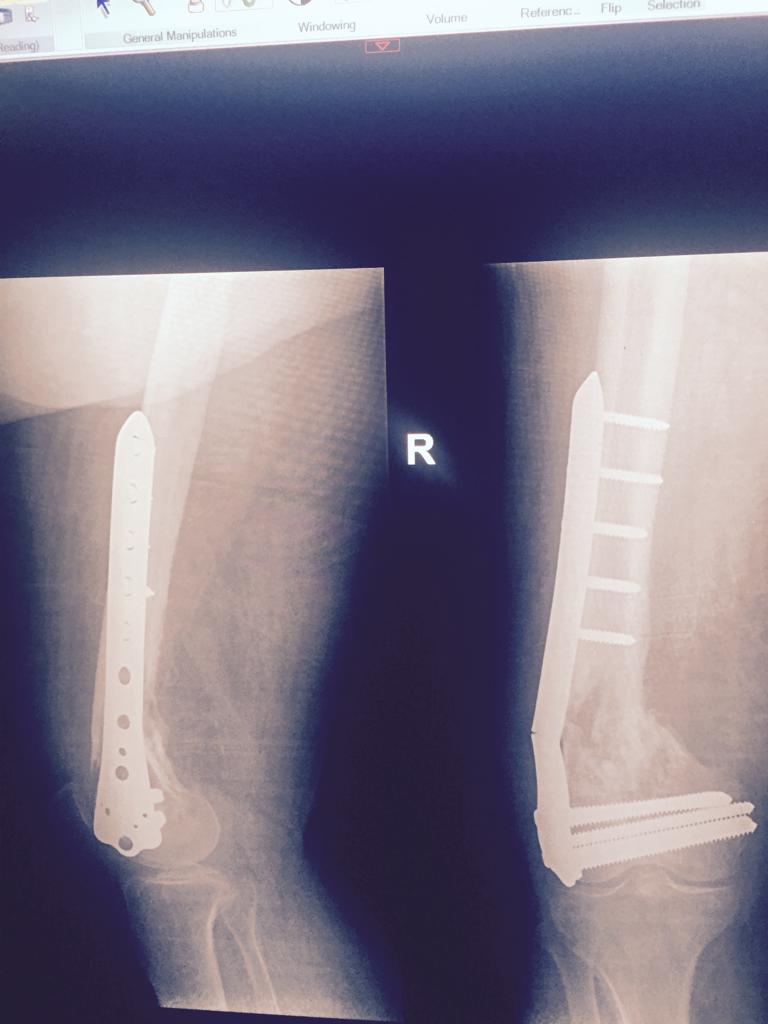

Total Knee Arthroplasty After a non-union